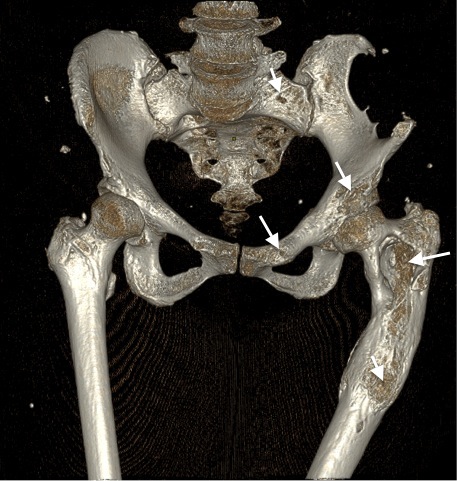

- На мультиспиральной КТ (МСКТ)левого тазобедренного и коленного суставов визуализированы зоны кистовидных перестроек и участков остеосклероза, преимущественно в области лобковой и седалищной костей, а также проксимальной трети левой бедренной кости; искривлена ось левой бедренной кости по типу «хоккейной клюшки». В структуре проксимальной и средней трети бедренной кости — две полости, содержимое которых представлено солидным содержимым, вероятно, фиброзной тканью. На уровне дистального отдела бедренной кости и проксимального отдела большеберцовой кости — множественные участки кистовидной перестройки, фрагментации костной ткани, местами с нарушением целостности и истончением кортикального слоя. КТ-картина соответствовала ФД (полиоссальная форма) костей таза слева, левой бедренной и большеберцовой костей (рис. 5–7).

Рис. 5. Пациентка М. Очаги фиброзной дисплазии в крыле подвздошной кости и в межвертельной области бедренной кости.

Рис. 6. Пациентка М. МСКТ таза, 3D-реконструкция. Полиоссальная форма фиброзной дисплазии. Зоны кистовидных перестроек (стрелки) в костях таза и левой бедренной кости, преимущественно расположенных в области подвздошной, лобковой костей, крестца слева, а также в проксимальной трети левой бедренной кости.

Рис. 7. Пациентка М. МСКТ левого тазобедренного сустава, корональная плоскость. Полиоссальная форма фиброзной дисплазии. Ось левой бедренной кости искривлена по типу «хоккейной клюшки». Шеечно-диафизарный угол 97° (норма 125–135°). Шейка деформирована, утолщена. В структуре проксимальной и средней трети бедренной кости определяются две полости (длинные стрелки). Содержимое полостей представлено солидным содержимым плотностью 65 ед. Н (фиброзная ткань). Кортикальный слой на границе проксимальной и средней трети неравномерно утолщен с периостальными костными наслоениями (консолидированный перелом?) (короткая стрелка).